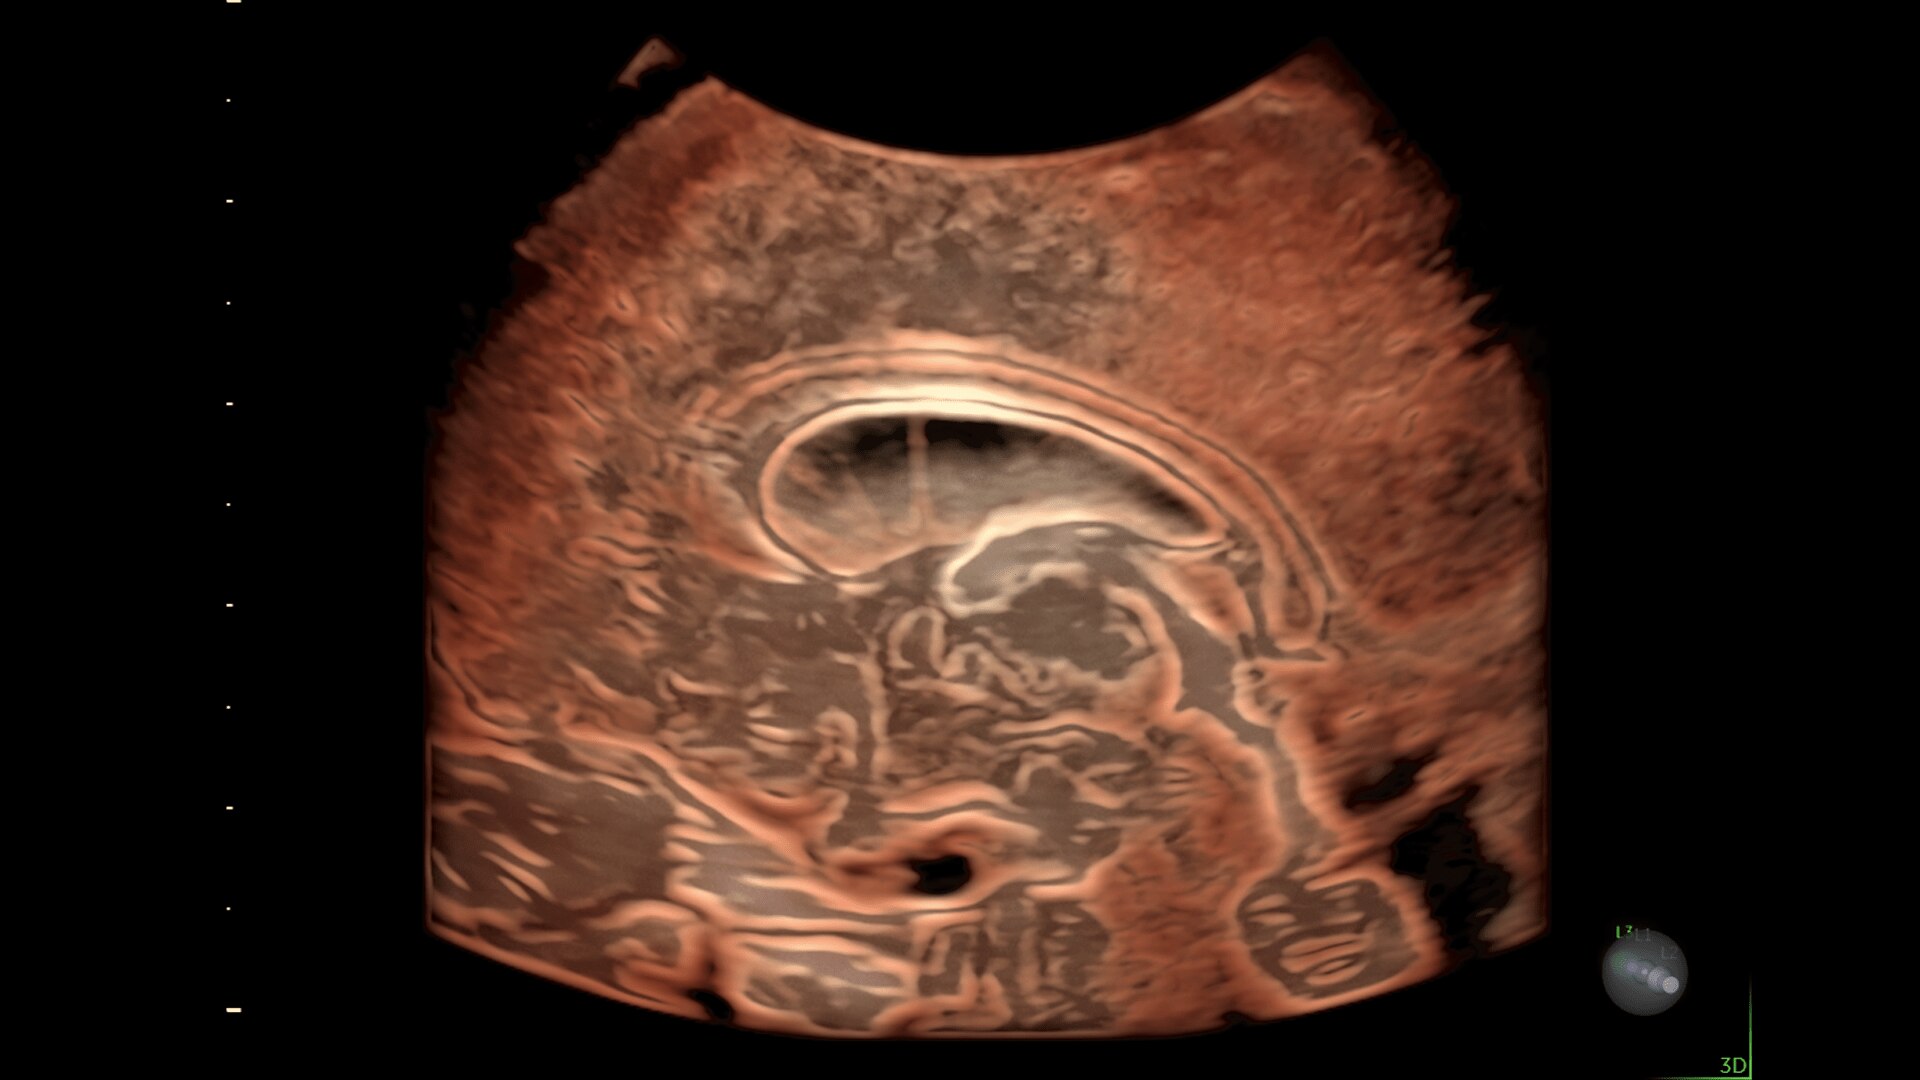

How to assess the fetal position